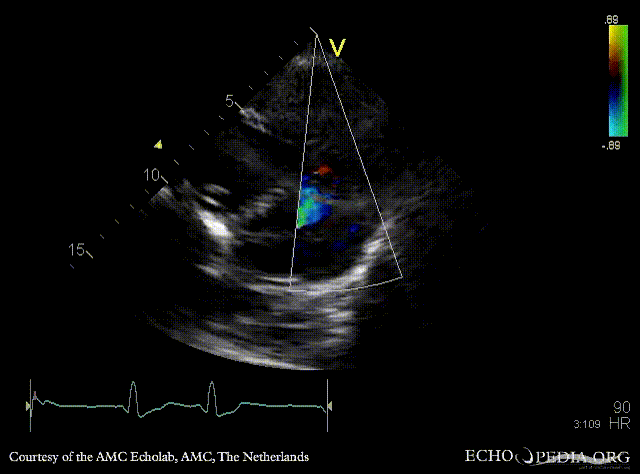

Apical VSD

Courtesy of: AMC Echolab, AMC, The Netherlands

A4CH: Apical VSD, bidirectional shunt Continuous-wave signal